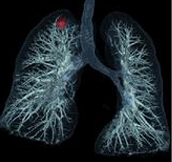

Lung area analysis software 3D display and automatic volume calculation for nodules.